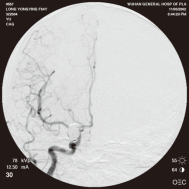

弹簧圈栓塞后造影示左椎动脉夹层动脉瘤消失, 左椎动脉、 多发动脉瘤夹闭术前、术中

左侧小脑后下动脉循环通畅